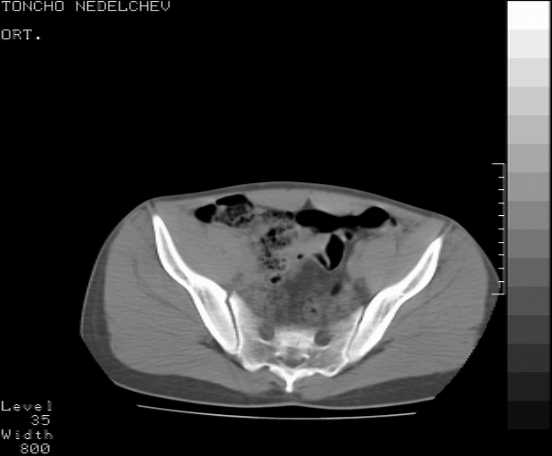

Re: Acetabular fracture

Here are some more axial images. What is your opinion as for the timing of the operative treatment?